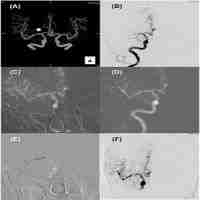

| Abstract | Objective: To investigate whether branch-site occlusion (BSO) sign could predict the etiology of acute intracranial large artery occlusion (ILVO) and the stentriever (SR) response. Methods: We systematically reviewed studies that evaluated the predictive role of BSO for the etiology of ILVO-AIS or EVT outcome between January 1, 2000, and August 31, 2022fromPubMed, Embase, and Web of Science. Results: The sensitivity and specificity of BSO sign predicting etiology of ILVO-AIS were 0.87 (95% CI 0.81-0.91) and 0.64 (95% CI 0.33–0.87), respectively(fig.3A). The sensitivity and specificity of BSO sign predicting stentriever response were 0.84 (95% CI 0.63-0.94) and 0.61 (95% CI 0.18-0.92), respectively. Conclusion: BSO sign could be a valid and precise imaging marker to predict embolism caused ILVO-AIS and recanalization success by SR without rescue therapy. |